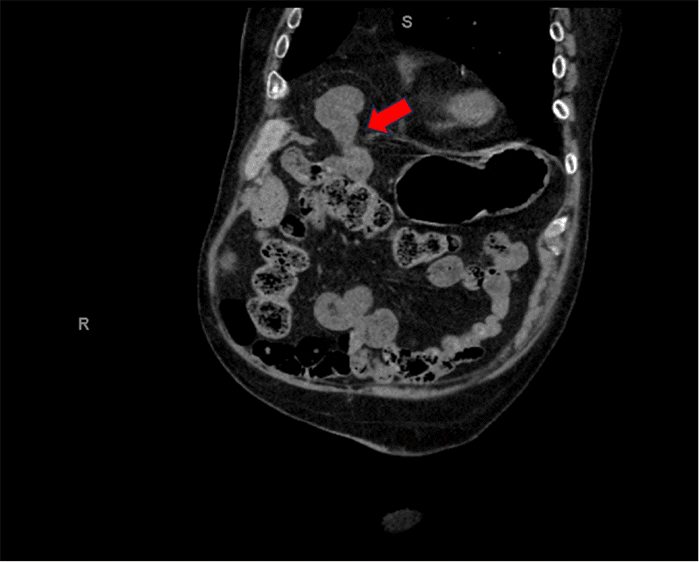

Figure 2. MRCP Demonstrating Gallbladder Hydrops. Published with Permission

MRCP image confirming marked gallbladder distension (hydrops, red arrow). The gallbladder measured approximately 13 cm in its maximum anterior-posterior dimension, and there was no evidence of biliary ductal obstruction